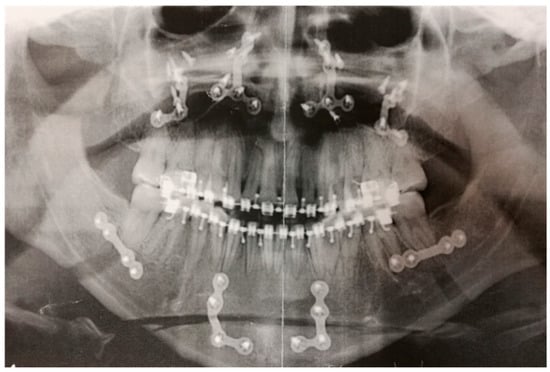

| Superinfection without necessity to remove of Osteosynthesis Devices | 8 | 13.79 |

| Superinfection and Removal of Osteosynthesis Devices | 5 | 8.62 |

| Reoperation | 4 | 6.89 |